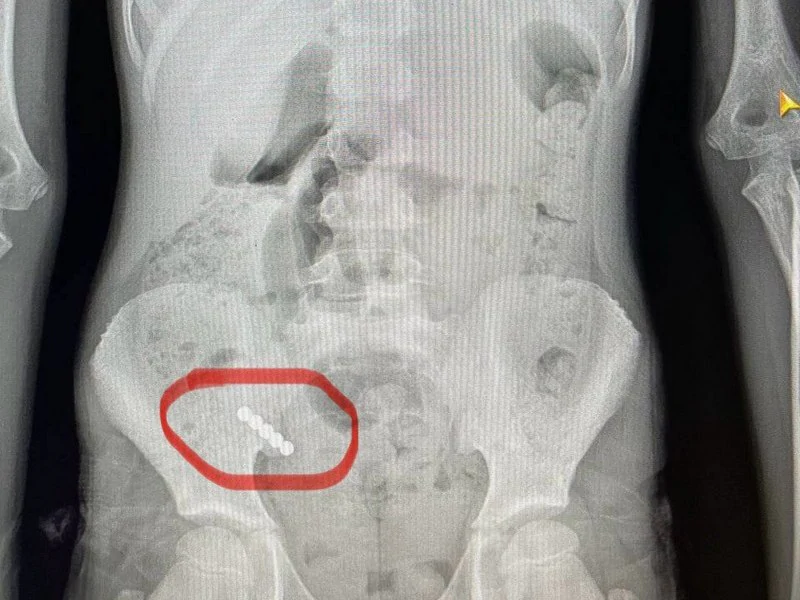

Під час операції лікарі виявили магніти, два з яких склеїлись між собою у різних відділах кишківника. В місці з’єднання утворився пролежень, а згодом — перфорація, внаслідок чого кишковий вміст витік у черевну порожнину.

«Непросто було видалити й магніти. Їх довелося «завести» в апендикс і видалити разом із ним. Дівчинку виписали додому на 10-й день після оперативного втручання», — Василь Демчук.